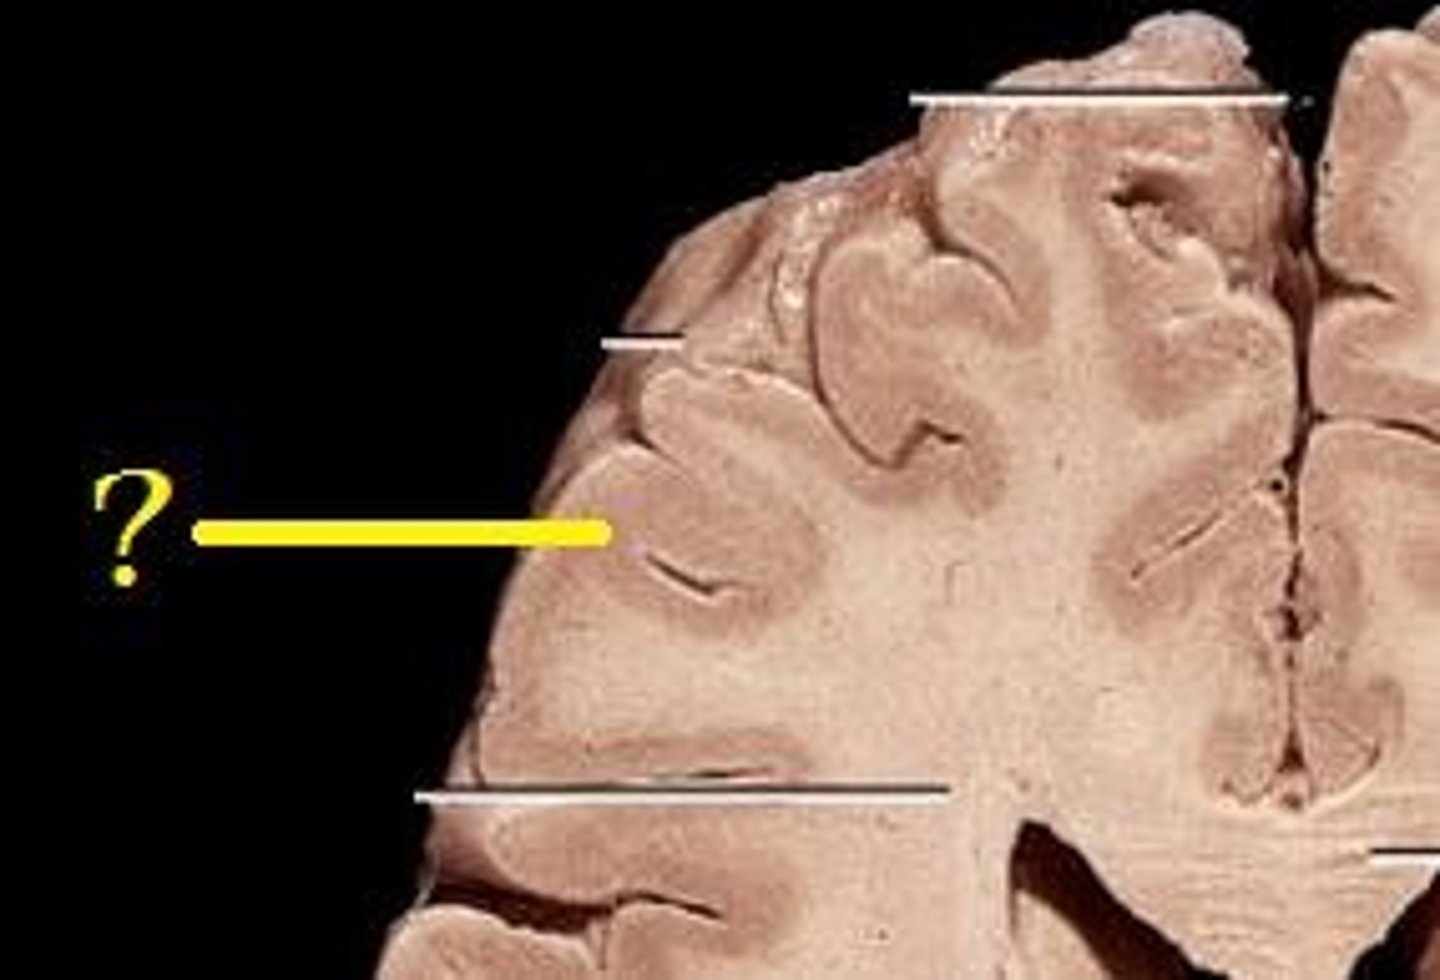

MIdsagittal View of brain

Lateral Ventricle

Third Ventricle

Cerebral Aqueduct

Forth Ventricle

Corpus Callosum

Fornix

Thalamus

Pineal Gland

Superior Colliculi

Inferior Colliculi

Midbrain

Hypothalamus

Cerebral Cortex Gray Matter (nerve cell bodies)

White Matter (myelinated nerve fibers)